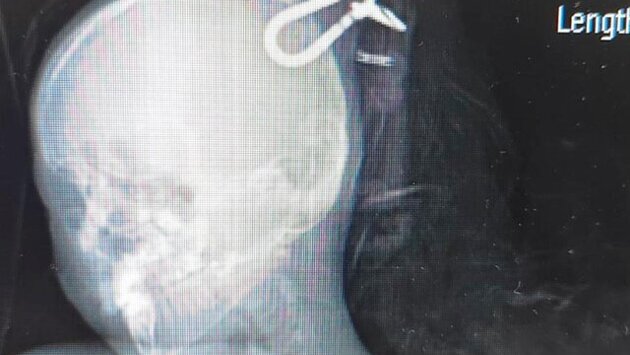

"Он занимался на тренажере в бассейне. Струна с разделительной дорожки ударила ему в голову. Фиксирующий крюк (карабин) разорвался и, проломив череп, вошел в мозг", – уточнил министр на странице в соцсети "ВКонтакте".

Врачам удалось изъять инородное тело, а после стабилизации пациента врачи перевезли мальчика в другое медицинское учреждение. Медики продолжают следить за ним, но сейчас ребенок может самостоятельно дышать.